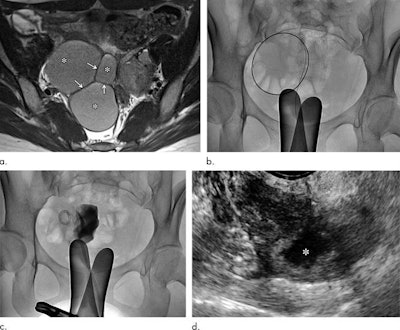

Catheter-directed sclerotherapy involves an interventional radiologist inserting a catheter rather than a needle under fluoroscopy guidance into the endometrioma to drain it. The radiologist then fills the cyst with contrast to determine whether any of its content has spilled into the pelvic cavity. The contrast is aspirated and ethanol injected into the cyst. After 20 minutes, the ethanol is removed and the catheter taken out.

The study included 14 women who had the procedure between March 2015 and December 2017. The researchers assessed the technique's impact on the women's ovaries by measuring serum anti-Müllerian hormone (AMH), an indicator of ovarian health, before and after the procedure and six months later. The group also measured serum cancer antigen 125 (CA-125) levels at these same time points to assess the procedure's effectiveness. Finally, study participants underwent follow-up ultrasound at one, three, and six months after catheter-directed sclerotherapy and biannually thereafter to track cyst size changes and/or recurrence.